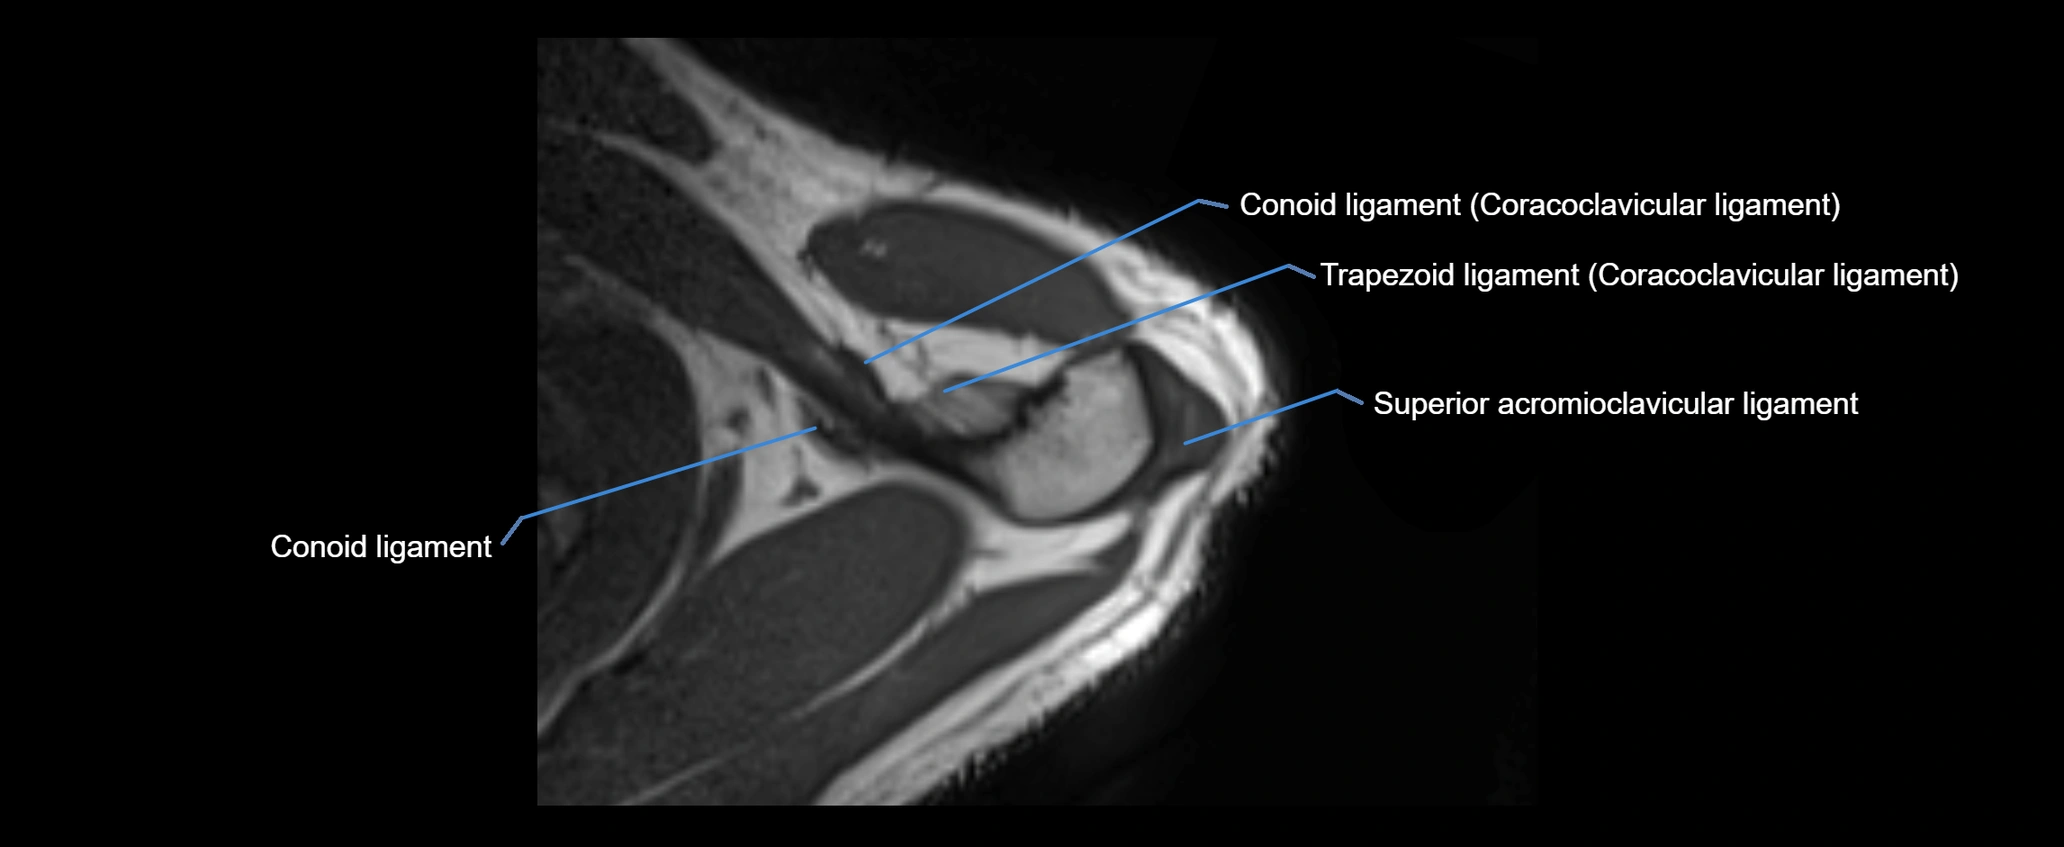

CT image

image

CT Appearance

Non-Contrast CT:

• Ligament: Not directly visualized due to small size and low density.

• Bony landmarks: Lateral clavicle and acromion clearly seen; cortical margins well defined.

• Pathology: Detects fractures, joint subluxation, osteophytes, and degenerative changes.

• Alignment assessment: Evaluates AC joint spacing and clavicular displacement.